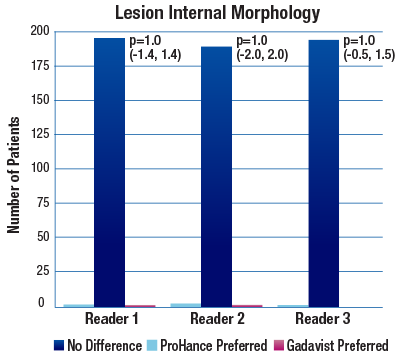

The 95% confidence intervals for all qualitative assessments confirm that ProHance is not inferior to Gadavist.1

No significant differences noted by any reader for any parameter:1

- Lesion Internal Morphology